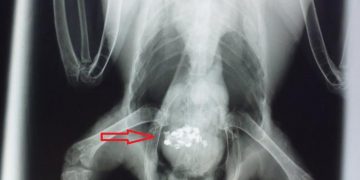

Evcil kuşlarda çinko zehirlenmesi (toksikozu). Çinko evcil kuşlar için birçok enzim fonksiyonu, deri sağlığı ve fertilite gibi çeşitli amaçlar için ...